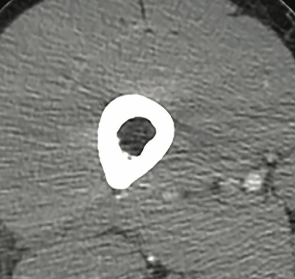

Urinalysis results were suggestive of urinary tract infection. Computed tomography scans of the abdomen/pelvis were obtained